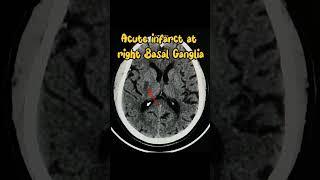

Acute infarct right MCA territory #infarct #headache #radiology #xray #biology #shorts

4D PARAMEDICAL TRANING CENTRE

Middle cerebral artery (MCA) Infarct (stroke) on CT brain #radiology #medicalstudent #doctor

Dr Azku | Radiologist

Thrombosed right middle cerebral artery resulting in acute cerebral infarct.

Learning Radiology from CT Scans with Prof Ashraf